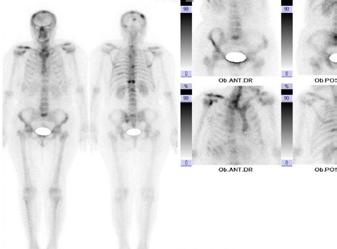

clinic: F, 63 ani, NET G2 ileon operată, cu determinări secundare hepatice, peritoneale, osoase, cu sindrom carcinoid în tratament cu analog de somatostatin și boală carcinoidă cardiacă. A-episod de flush; B-scintigrafie osoasă cu modificări osteogenice cu aspect de leziuni secundare multicentrice; C-aspect ecocardiografic de regurgitare tricuspidiană moderat-severă; D-aspect morfopatologic al determinărilor secundare hepatice, x30; E-chemoembolizare hepatică transarterială (TACE)

A B C D E

Figura 1. Caz